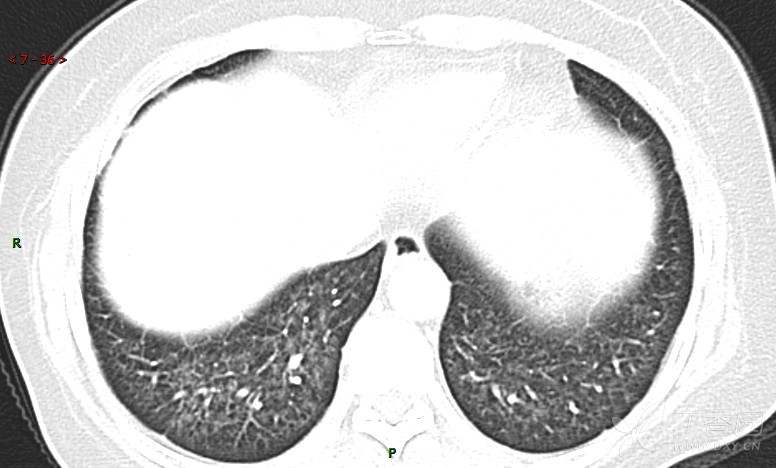

肺内弥漫性网状结节影,PET-CT却无阳性病灶,这是?(附其他2例链接)

患者于2月前无明显诱因出现咳嗽,以阵发性干咳为主,接触冷空气后咳嗽明显,偶咳少量白色泡沫样痰,咳嗽剧烈时感憋喘,无发热、盗汗,无头痛、头晕,无胸痛、咯血,无恶心、呕吐,无腹痛、腹泻,无尿频、尿痛等不适,于当地医院给予肌注及静脉药物治疗,具体药物名称不详,效果欠佳,近1月来患者咳嗽频率较前增加,咳嗽剧烈时感双侧季肋区疼痛不适,10余天前出现发热,体温在38℃左右,伴畏寒、寒战,无头痛、头晕,无纳差、乏力等不适,药物治疗后体温降至正常,仍阵发性咳嗽,今为求进一步诊治,就诊于我院急诊,因呼吸内科暂无床位,急诊门诊以“肺间质病变”收入急诊留观室,给予“抗感染、止咳”等对症支持治疗后,今日以“肺间质性病变”收入我科,患者自本次发病以来,神志清,精神可,饮食尚可,睡眠一般,大小便正常,体重较前无明显变化。

患者活检肺组织后行PET/CT检查